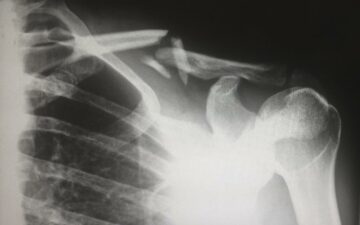

Portable X-ray Machines Revolutionize Healthcare in Remote Communities

Portable X-ray machines are emerging as a transformative healthcare solution, particularly for remote patients. These devices can literally be the difference between life and death, offering unparalleled advantages for acutely unwell patients and infection control.

Traditionally, X-rays are performed in hospitals, requiring patients to undergo the additional burden of transportation. However, portable X-ray machines eliminate this challenge by bringing the equipment directly to the patients. This is particularly beneficial for remote locations such as battlefields, disaster zones, and roadside emergencies.

Portable X-ray machines come in two main types: mobile machines on wheels and ultraportable devices that can be carried by a single person. The latter, exemplified by the Fujifilm Xair weighing only 3.5kg, has proven to be a game-changer in remote areas like the Orkney Islands in Scotland. During a trial, non-attendance for X-ray appointments was reduced to zero, offering a more accessible and efficient healthcare solution.

Advancements in technology have addressed previous concerns about image quality, with today’s portable X-ray machines rivaling their fixed counterparts in diagnostic standards. However, challenges remain, including limitations in component size, battery life, and data storage, impacting the number of patients that can be imaged in one session.